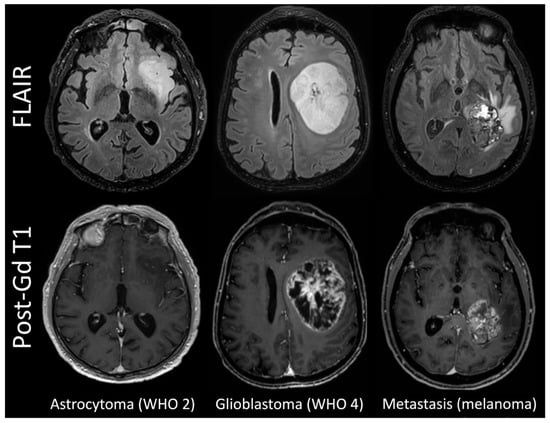

The WHO 2 gliomas tended to be more homogeneous on FLAIR images and have no contrast enhancement on T1-weighted images, whereas most WHO 3 gliomas showed discrete foci of enhancement; glioblastomas and metastases presented as large lesions with central heterogeneous enhancement surrounding necrosis and peripheral oedema on FLAIR images (Figure 1).

Figure 1.

FLAIR and post-contrast T1w images in representative cases.